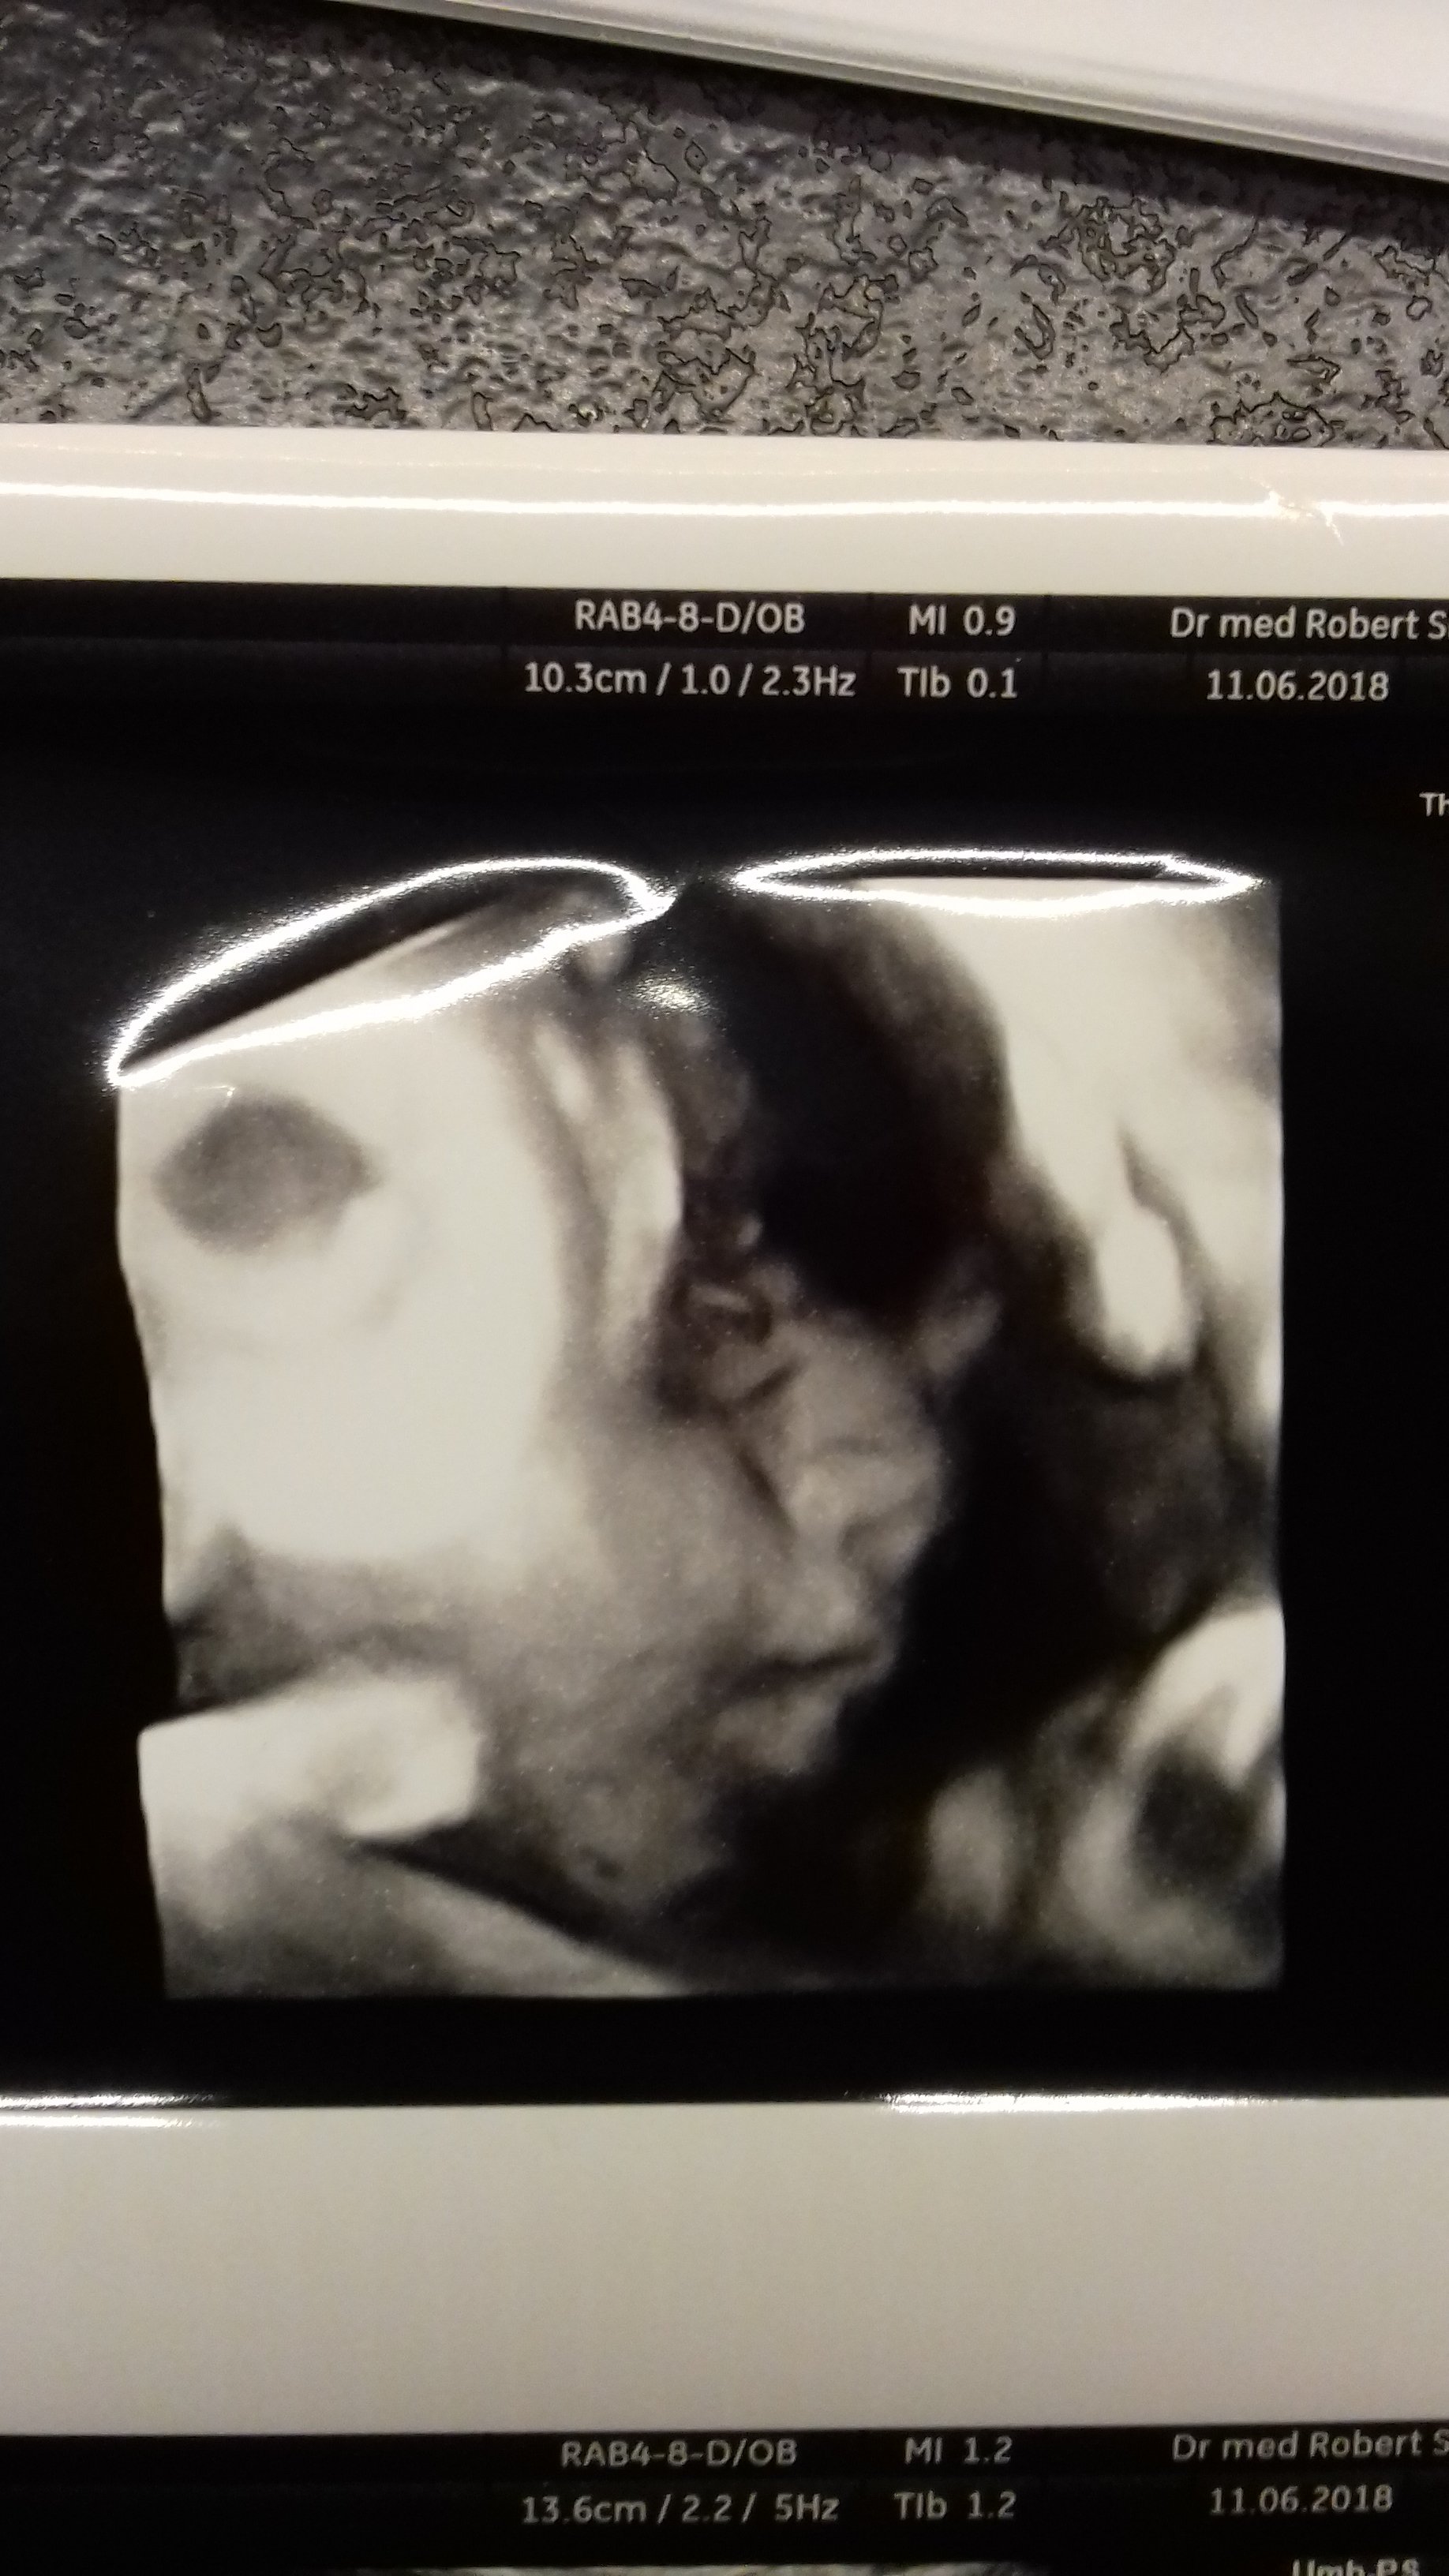

20180611_215824.jpg

Taki dziubek tylko udało się uchwycić. Już się nie mogę doczekać, kiedy go cmoknę w ten pyszczek ❤❤❤

• 20180611_215824.jpg

581,2 KB · Wyświetleń: 373